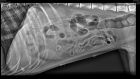

- Leverera en hög och stabil bildkvalitet